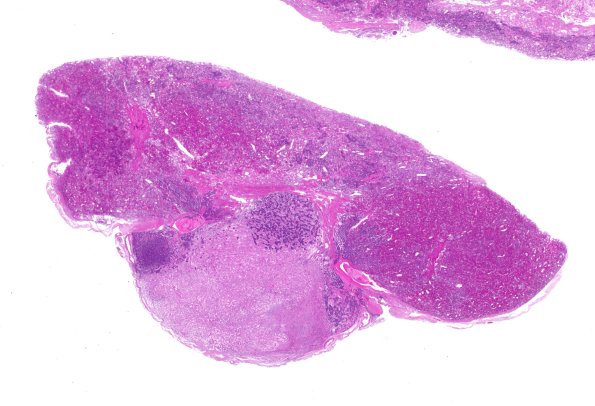

6C1 Pituitary, normal basophil invasion H&E WM

6C1-3 Increasing magnification of basophil invasion. (H&E)